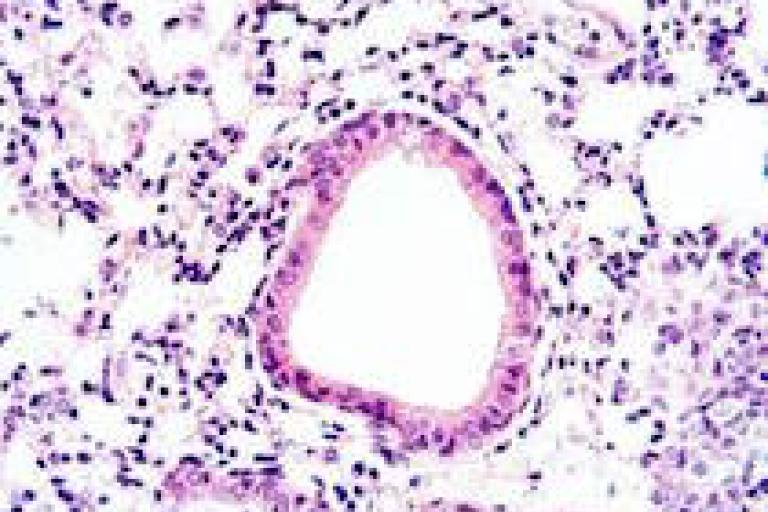

Image: Histology of lungs from our mouse model of Pseudomonas aeruginosa infection.